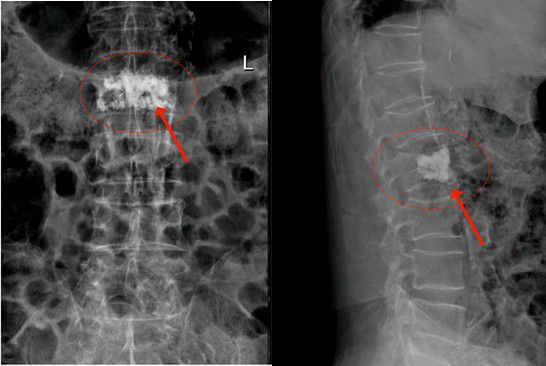

經内科綜合治療後,2月14日陳大伯身體各項指征平穩,可耐受手術。吳主任根據術前方案,爲老人家實施椎體成形術。在我院先進的術中三維CT機引導下,準确将2根穿刺針經雙側椎弓根穿入骨折椎體内,通過穿刺針建立通道注入骨水泥。術中三維CT機監視骨水泥分布良好,順利完成手術。手術切口小,無須縫合。由于采用局麻,術中陳大伯甚至還可以和醫護人員對話。注入的骨水泥支撐起原本空洞的椎體,骨水泥凝固後使病變的椎體迅速恢複了承重能力。

△術後,病變的椎體迅速恢複了功能